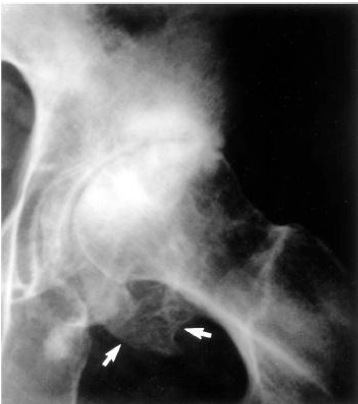

HyperPTH leading to 2o osteoporosis

Osteitis fibrosa cystica: Brown tumour (Gross image)

Etiology

Increased PTH resulting in increased osteoclast activity.

1° - adenoma – high Ca, low PO43-

2° - renal failure – low Ca, high PO43- (opposite levels vs 1o)

3° - initially secondary cause that turned primary due to cellular adaptive change

Sx: Stones, Bones, Moans